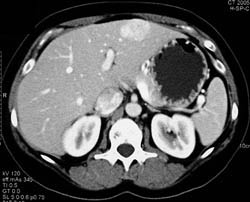

Focal Nodular Hyperplasia (FNH)